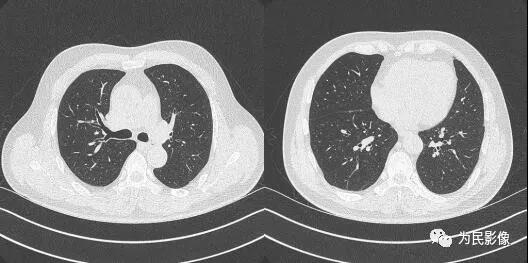

下面是我科利用雙源CT采用低劑量+高分辨+迭代重建的圖像及放射劑量。

患者圖像:

(在保證圖像質(zhì)量的前提下,新技術(shù)放射劑量明顯低于常規(guī)掃描患者的輻射劑量。)

我科胸部CT采用高分辨(HRCT)圖像讀片,避免因?qū)雍裨驅(qū)е滦〗Y(jié)節(jié)漏診。但每個(gè)患者的圖像有數(shù)百幅之多,帶來(lái)醫(yī)生工作量的增加。